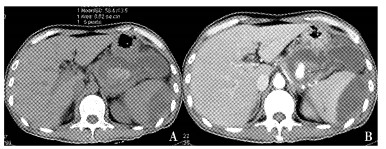

结果  6例假性动脉瘤中3例位于脾动脉, 另3例分别位于胃十二指肠动脉、胃网膜右动脉和胰十二指肠下动脉。增强CT发现4例, 全部通过数字减影血管造影(digital subtraction angiography, DSA)明确诊断并采取经导管动脉栓塞治疗, 技术成功率和临床成功率达100%, 无严重并发症发生。

Results  The locations of these 6 pseudoaneurysms included splenic artery (n=3), gastroduodenal artery (n=1), right gastroepiploic artery (n=1), and inferior pancreatioduodenal artery (n=1). Four pseudoaneurysms were detected by contrast-enhanced computed tomography (CT) and all were showed in digital subtraction angiography (DSA). TAE was performed as the first-choice management and the hemorrhage was controlled in all cases. Both the technical and clinical success rates reached 100% and no major complications occurred.